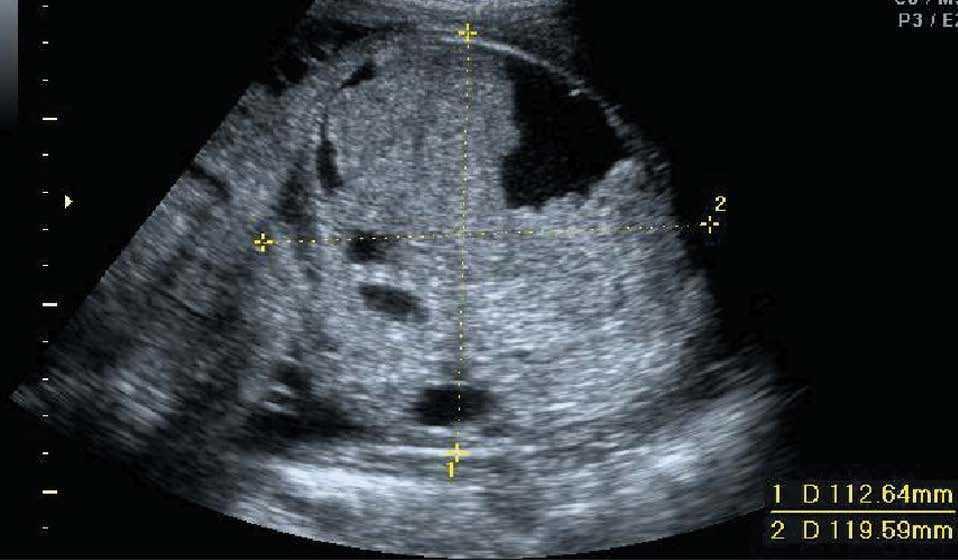

En la siguiente exploración ecográfica, en la semana 25 + 3, se observó un crecimiento de la tumoración con diámetros de 91 × 97 × 91 mm (fig. 3). No se observaban signos de sobrecarga cardíaca, y el Doppler del ductus venoso y la arteria cerebral media eran normales. Como hallazgo adicional a la ecografía anterior, se constató una pielectasia bilateral de 9 mm y un hidramnios (ILA 28) (fig. 4).

Figura 3. Ecografía realizada en la semana 25, donde se observa el crecimiento de la tumoración que mide 91 × 97 × 91 mm.

Figura 4. Ecografía realizada en la semana 25, donde se aprecia una pielectasia bilateral de unos 9 mm.